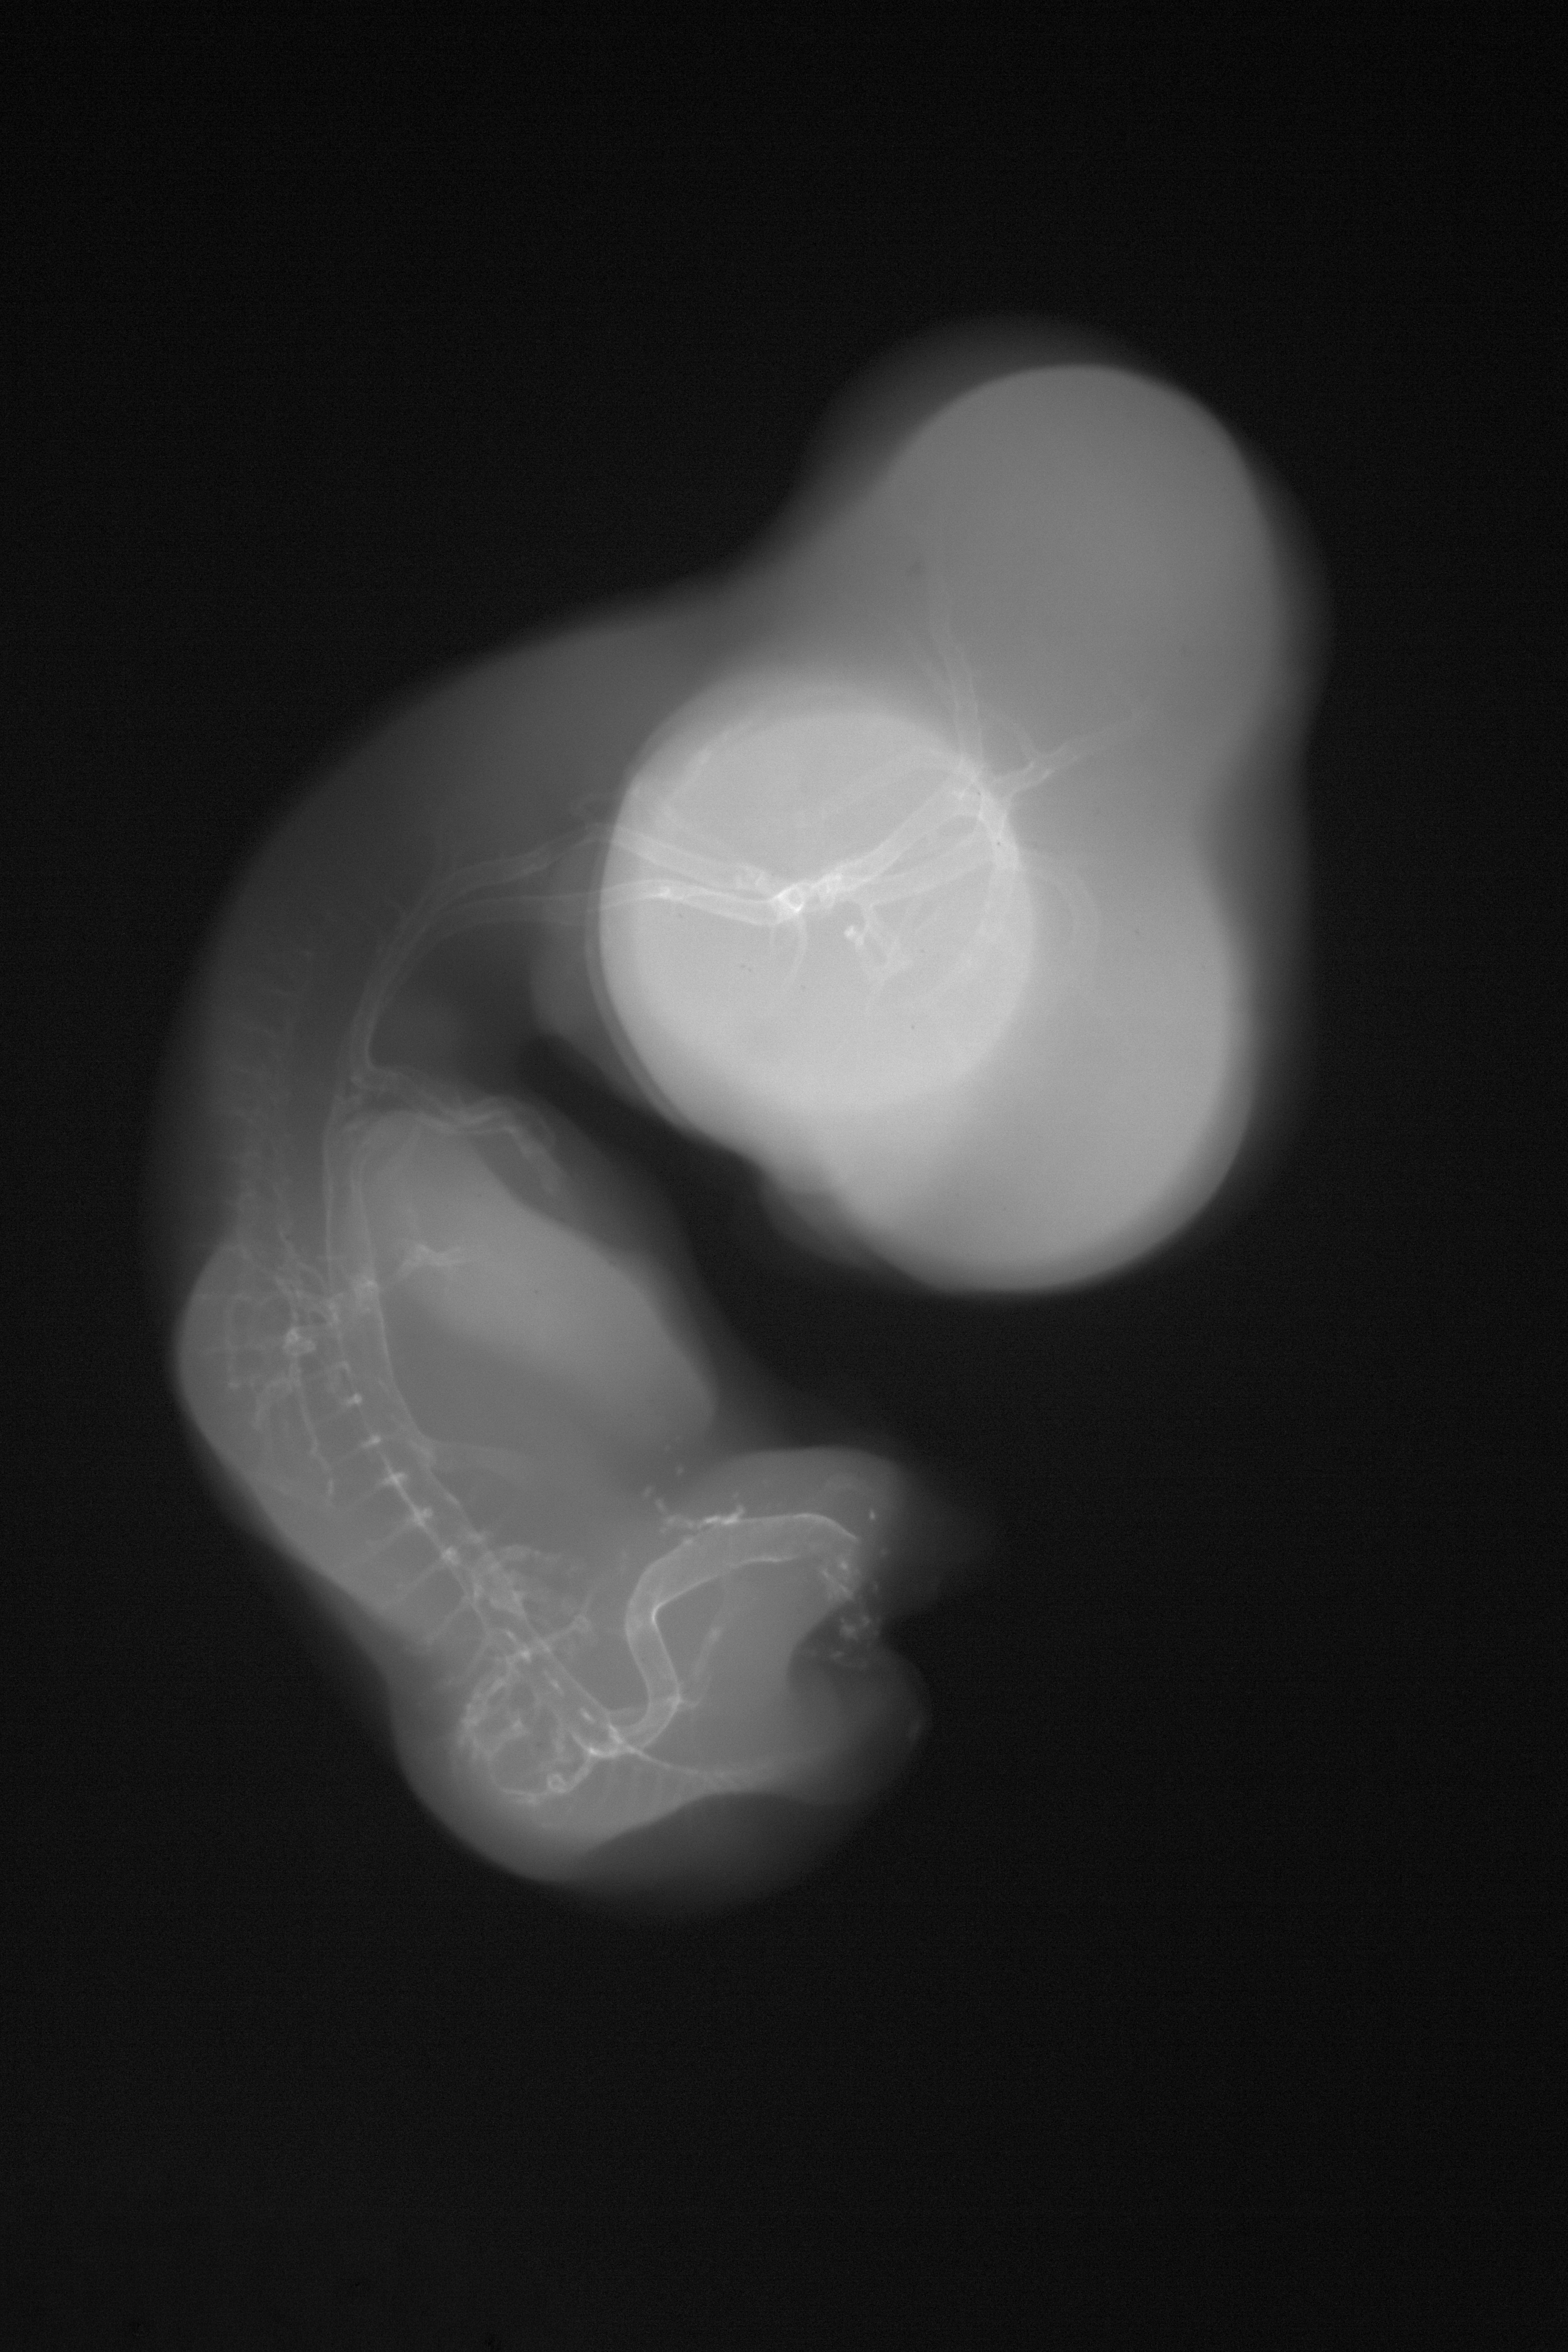

Hamburger-Hamilton (HH) Stage 29 (approx. 6 - 6.5 days)

X-Ray Micrographs